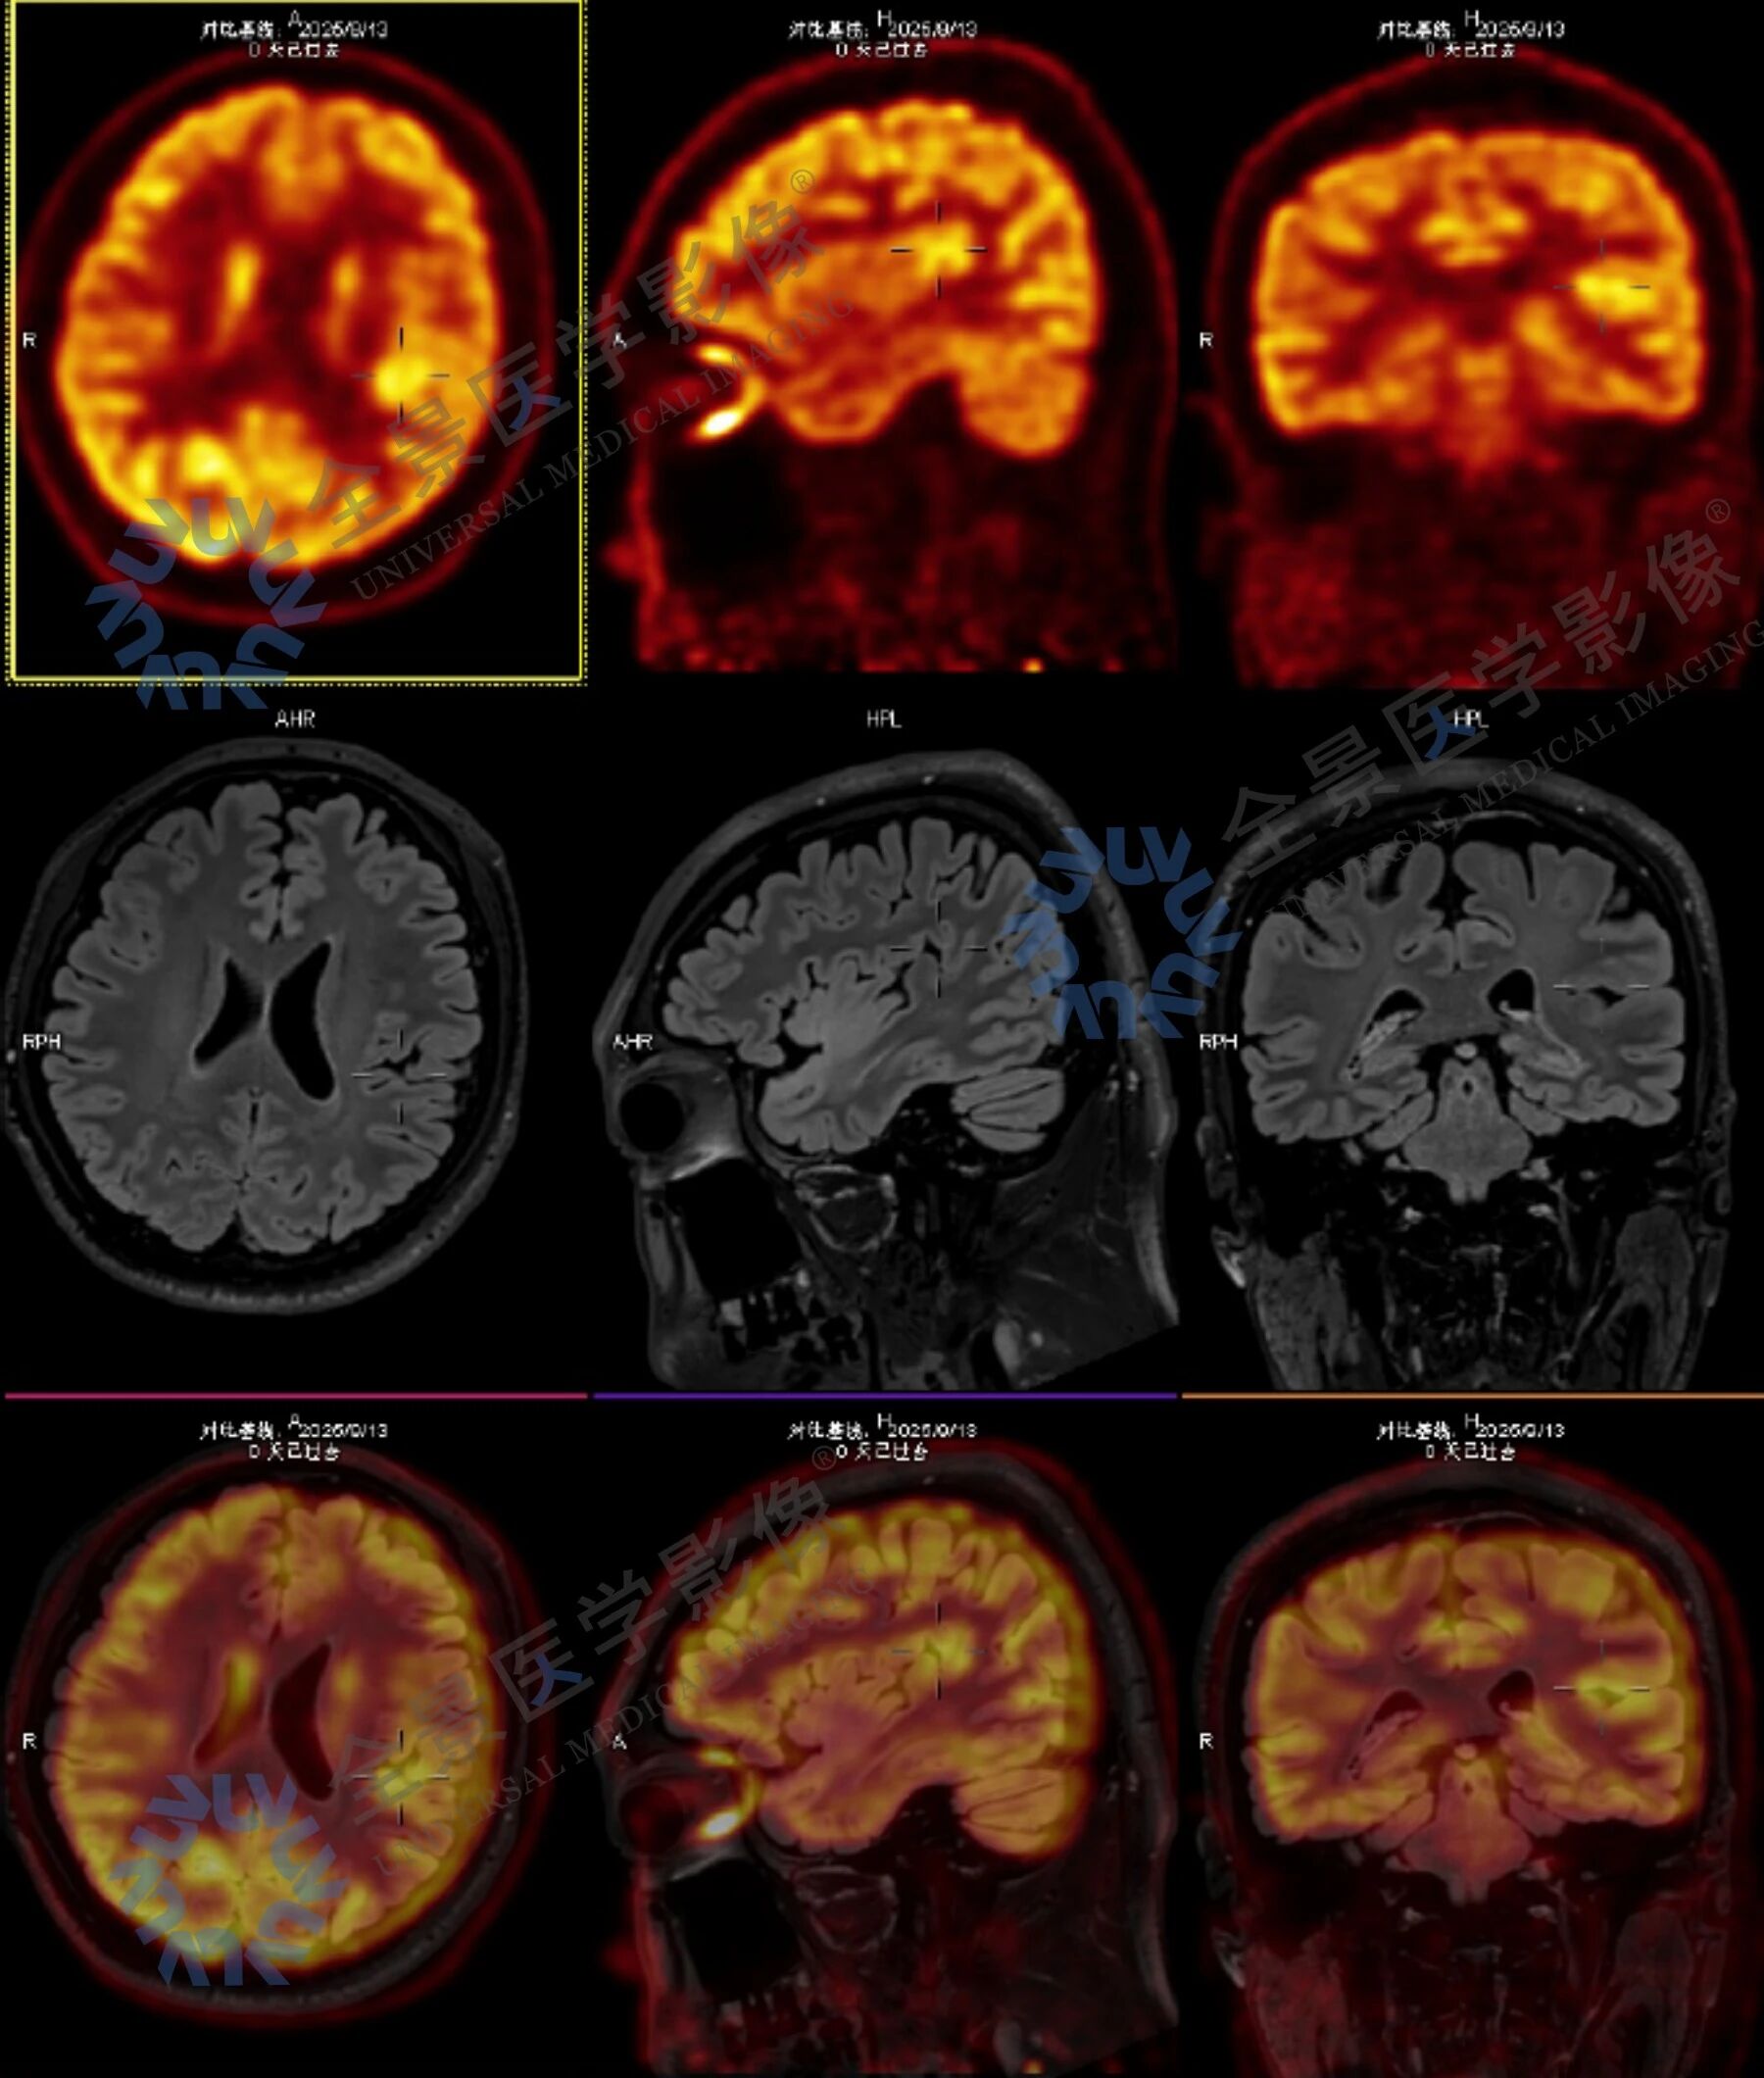

考虑到病症复杂,全景安排门诊部主任与影像主任联合问诊,结合病史和症状,影像主任建议在无创检查前提下,采用结构影像、血流灌注与代谢功能的多模态联合检查,通过脑部 MR 平扫、ASL 脑血流灌注成像与脑部 PET-CT 的融合,实现精准定位与定性诊断。

脑部核磁+ASL 脑血流灌注成像显示:

左侧基底节区异常信号,考虑术后改变,局部脑软化灶周围胶质增生;相应区域 ASL 示灌注稍减低。

脑部 PET-CT 扫描显示:

病灶前缘 MR 异常信号增高,考虑局部神经胶质增生表现;左侧上额叶中部深层较小的类圆形代谢轻中度增高灶及左侧颞叶中部后内侧小片状轻中度代谢增高灶。

结合影像检查结果与临床表现,考虑上述三个部位与头晕发作关系密切,提示存在癫痫可能,以左侧颞叶中部后内侧代谢增高灶为主要病变部位。